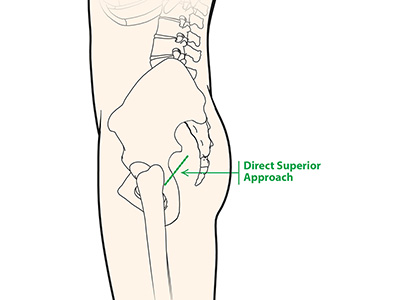

Direct Anterior Hip Replacement Direct Superior Hip Replacement

Direct Superior Hip Replacement Bikini Incision Hip Replacement